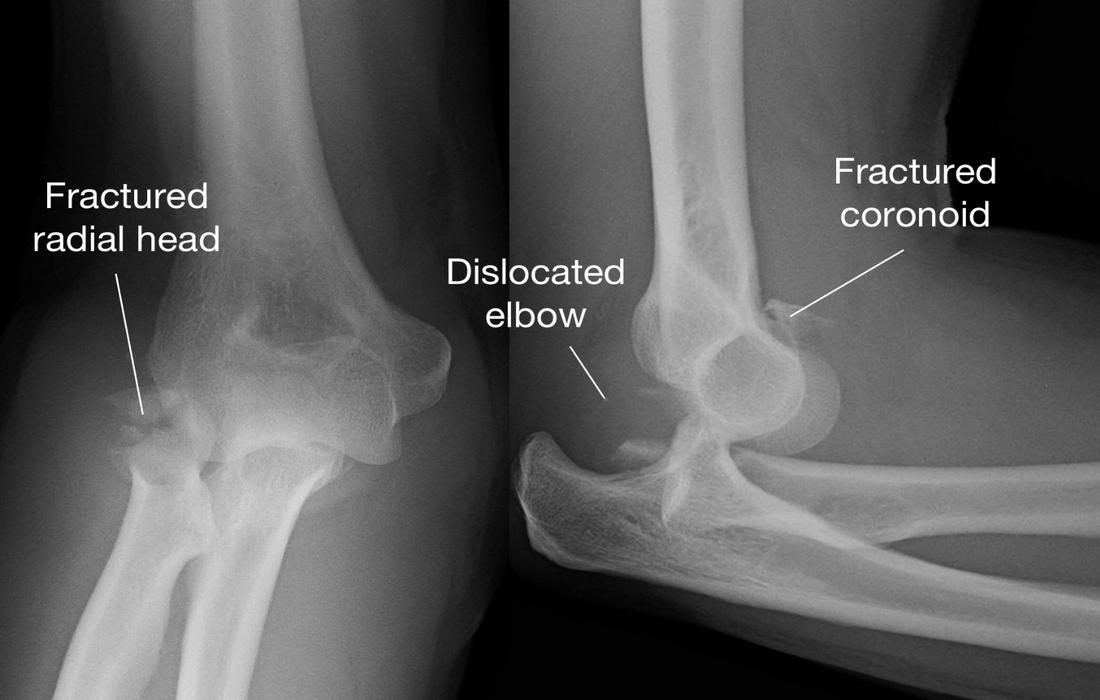

Κάταγμα Κεφαλής Κερκίδας

Η κεφαλή της κερκίδας βρίσκεται στην έξω πλευρά του αγκώνα και βοηθά στην κίνηση στροφής του αντιβραχίου.

Αίτια: συνήθως προκαλείται από πτώση στο τεντωμένο χέρι.

Συμπτώματα: πόνος στην έξω πλευρά του αγκώνα, δυσκολία στη στροφή του χεριού, πρήξιμο.

Κάταγμα Ωλεκράνου

Το ωλέκρανο είναι η “μυτερή” απόφυση που ψηλαφούμε στο πίσω μέρος του αγκώνα.

Αίτια: συχνά συμβαίνει μετά από πτώση απευθείας στον αγκώνα ή από έλξη του τρικεφάλου.

Συμπτώματα: έντονος πόνος στο πίσω μέρος, δυσκολία στην έκταση του αγκώνα, ορατή παραμόρφωση σε ορισμένες περιπτώσεις.